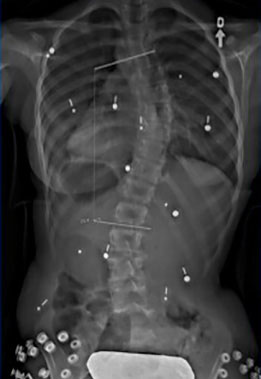

Étude de cas d’une autre adolescente avec une scoliose

Le cas d'une adolescente âgée de 12 ans et 9 mois (Risser 0) au début du traitement.

Cette jeune fille, dont la photographie montre une difformité importante du dos, souffre d’une scoliose déjà sévère dont la courbe atteint 42° (angle de Cobb) au début du traitement.

Dès l'installation du SpineCor®, on note une réduction de la courbure grâce à l'action dynamique des bandes élastiques malgré une scoliose très importante.

Après 30 mois de traitement, la scoliose est stabilisée à 33° et la croissance terminée. Il est normal avec une courbure d'amplitude aussi marquée de remarquer une légère perte de correction par rapport au premier jour du traitement, car la colonne vertébrale de la patiente a continué de grandir durant le traitement et la courbe d'évoluer. Quand on débute plus jeune le traitement sur des scolioses de moindre amplitude, il est souvent possible d'éviter ces phases d'aggravation.

Mais au final, la dernière photographie prise après le sevrage du traitement montre clairement que la posture de la jeune fille présente un aspect beaucoup plus normal et symétrique qu'au début. Grâce à SpineCor®, l'esthétique de son dos s'en trouve améliorée encore plus que la correction réelle de sa courbe, ce qui aura inévitablement un effet positif direct sur son image de soi.